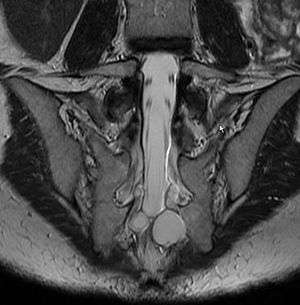

MRI image showing a Tarlov cyst.

MRI, or Magnetic Resonance Imaging, is considered the imaging study of choice in identifying Tarlov cysts. MRI provides better resolution of tissue density, absence of bone interference, multiplanar capabilities, and is noninvasive. Plain films may show bony erosion of the spinal canal or of the sacral foramina On MRI pictures, the signal is the same as the CSF one.